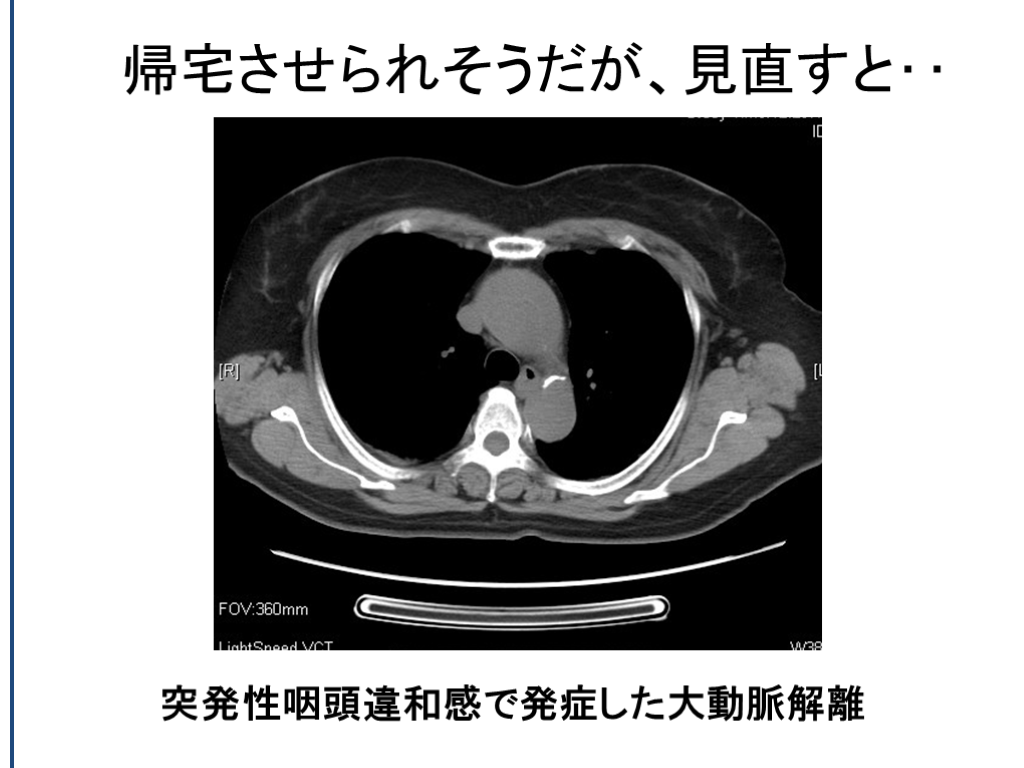

帰宅させられそうだが、見直すと‥ 突発性咽頭違和感で発症した大動脈解離